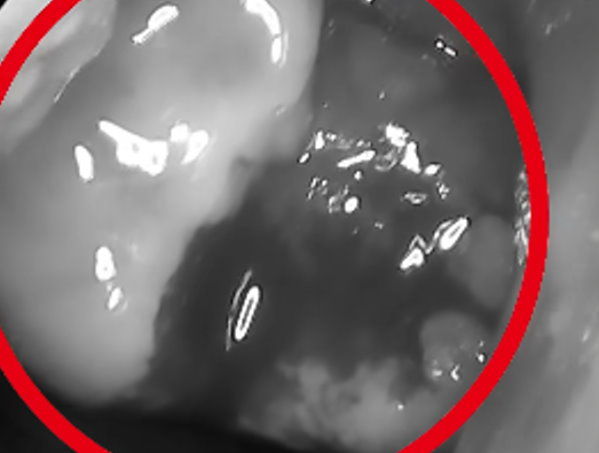

▲當事人診斷鼻咽癌。(圖/翻攝「陳亮宇醫師 / 陳亮宇耳鼻喉科診所」臉書)

陳亮宇指出,患者一開始去其他診所,起初醫師只換了幾次抗生素,但症狀仍未改善;後來到他的診所看診,經過檢查後,發現鼻咽部有一顆大腫瘤,切片證實是鼻咽癌,後續緊急轉醫學中心治療。